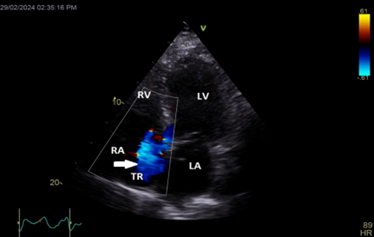

Color Doppler mapping of the tricuspid valve showed severe tricuspid regurgitation (TR) (Figure 5).

Figure 5: Apical 4 chambers view showing severe tricuspid regurgitation (white arrow).

LA=left atrium; LV=left ventricle; RA=right atrium; RV=right ventricle; TR=tricuspid regurgitation